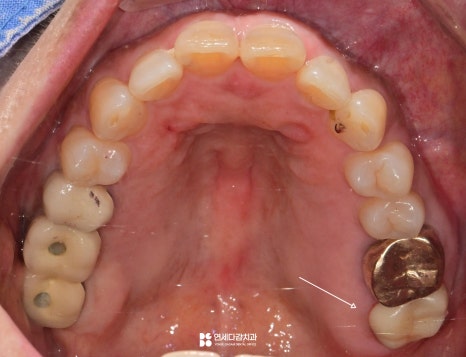

이렇게 눈으로 살펴봤을 때는

특별한 이상은 없는 것처럼 보이지만,

실제로는 통증을 느끼는 경우가 있습니다.

이는 구강 안에 육안으로 확인하기 어려운

사각지대가 존재하기 때문입니다.

이 사각지대 중 하나가 인접면입니다.

치아의 옆면은 음식이 자주 끼는 곳이지만,

이물질을 제거하기 어렵고 확인도 어렵기 때문에

우식이 자주 발생하는 부위입니다.